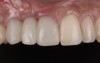

At the patient’s return visit 3 months after implant placement, the composite overlays were removed and the incisal edges of the provisional restoration were modified to approximate the length of the contralateral teeth. The patient reported no complaints, discomfort, or symptomatology throughout the osseointegration period. The implants were stable, and all discernable clinical parameters were within normal limits. The radiographic assessment revealed adequate bone-to-implant contact and osseous crest levels. Similarly, the peri-implant soft tissues displayed a healthy appearance and satisfactory gingival margin architecture (Figure 24 through Figure 27).

In this case report, the tridimensional reconstruction of a complex iatrogenic defect was accomplished using orthodontic forced eruption to restore the vertical height and minimally invasive bone grafting to achieve horizontal augmentation.27,29,48 This interdisciplinary approach allowed the predictable development and preservation of favorable peri-implant soft tissues. Gingival volume, margin level, and architecture were successfully restored while avoiding multiple hard- and soft-tissue grafting procedures. The only shortcoming was the length of the papillae adjacent to the area of the defect, which did not match the contralateral side.

Fig 25. Three months post-treatment, peri-implant soft tissues appeared healthy.

Figure 25

Fig 26 . Three months post-treatment, favorable gingival architecture was preserved.

Figure 26

Fig 27. Three months post-treatment, favorable gingival architecture was preserved.

Figure 27